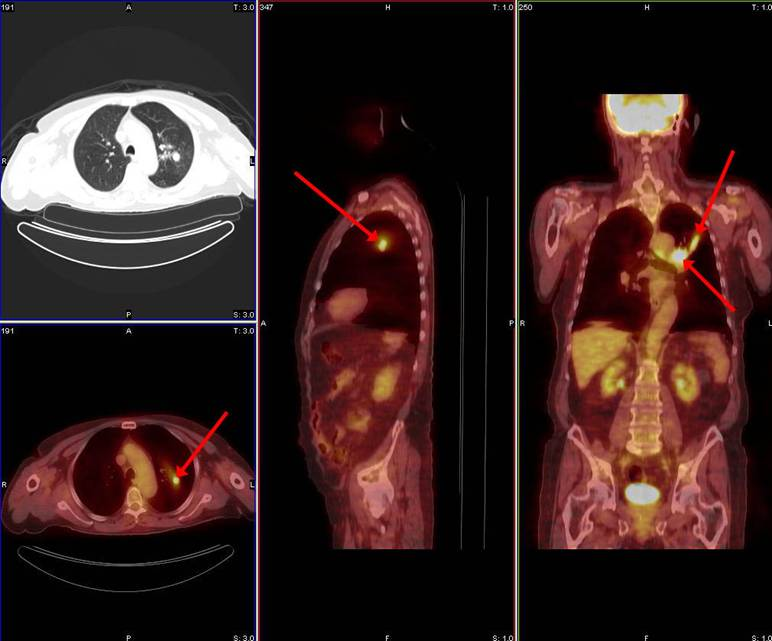

In 1998 a PET F-18 FDG study for solitary pulmonary nodules was successfully reimbursed by an insurance company

What are solitary pulmonary nodules?

Tumors that can be benign or malignant

Based on the PET scans, biopsies will only be done on the tumors that had high uptake of the FDG

Why were solitary pulmonary nodules reimbursed first by insurance companies?

Before, patients would biopsy all and every nodule that was found as probable for cancer

With solitary pulmonary nodules and PET, it allowed physicians to determine if the nodules were potentially cancerous and if biopsies were even needed – more cost effective

What is the most commonly used radiopharmaceutical in PET?

F-18 FDG

Breakdown what PET/CT is a combination of (what each part specifically scans)

PET – scans the patient’s physiology

CT – scans the patient’s anatomy

What type of process is commonly seen in cancer?

Metabolic process – hypermetabolic

What is metabolism?

The process of taking up glucose and using it as energy

Why do we like to use FDG as a pharmaceutical in PET?

It’s a sugar that is very similar to glucose

As cancer uses metabolic processes, it uses glucose as its main form of energy – we take advantage of this by binding the radioactive material with a pharmaceutical that’s similar in structure to glucose so that we can visualize where the cancer is based on its metabolism

What happens to the FDG when it’s up-taken by the cancer cells?

Instead of breaking down FDG and using it as energy, it will just accumulate in the cancer cell – makes the cancer more visible on our PET images